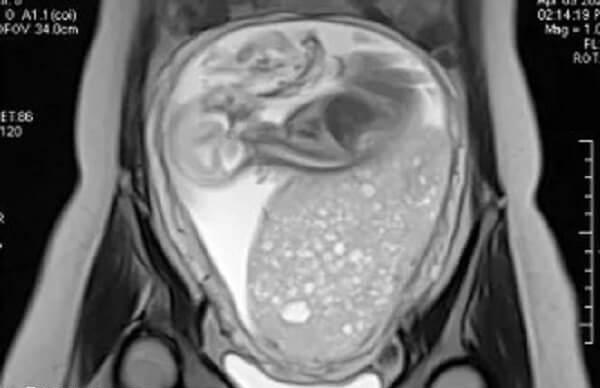

试管婴儿移植后,部分患者可能会出现一些特殊的妊娠并发症,比如葡萄胎,这是形状类似于葡萄样水泡样得名而来。一般葡萄胎常见于早期妊娠,其病因尚未完全明确。但根据医学研究,一般认为葡萄胎多数情况下是由染色体异常引起的,其中男方和女方都有可能存在异常。